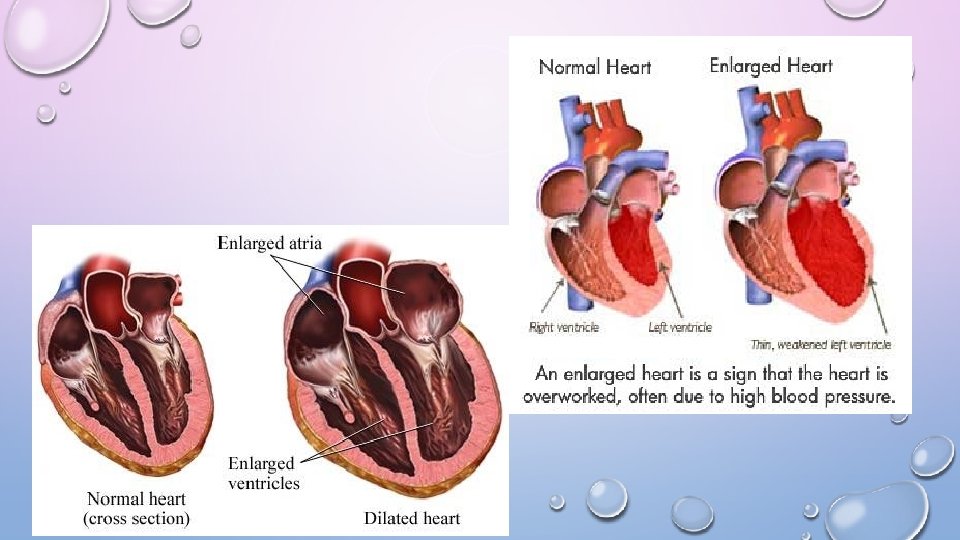

ENLARGED HEART (CARDIOMEGALY) • LEADS TO CONGESTIVE HEART FAILURE, CANNOT PUMP BLOOD NORMALLY, WALLS BECOME THIN AND STRETCH • CAUSES: VIRAL, KIDNEY DISEASE, DRUG ABUSE, GENETIC, HIV • BLOOD DOPING- INCREASE RBC, INCREASE CONCENTRATION OF OXYGEN